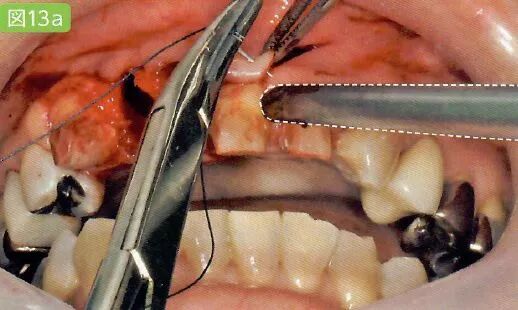

3 切开

利用手术刀·电刀等器械将手术区域的牙龈切开

医生利用手术刀进行切开。首先避免吸唾器在手术刀的切开路线上阻碍医生的操作。切开线设计分为三角形,四边形和沿牙龈缘等各种不同的形状。口腔卫生士一定要事先与医生确认切开设计的形状。

切开线设计(有残根的情况)

务必保证切开线区域的视的野晰度(切开前要吸引唾液,切开过程中要吸引血液)

切开前,一定要将切开线区域的唾液吸引干净。如果切开区域有唾液残留的话,会造成医生无法找到切开线路。切开时,从切开线区域会有血液溢出。将吸唾器放置到出血点,正确找到出血点才能更加有效的将溢出的血液吸引干净。